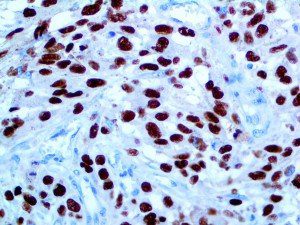

It is the ICU physician who is most likely to witness one of the deadliest manifestations of the abnormal immunological response, the cytokine storm syndrome (CSS). This response is also referred to by some as the cytokine release syndrome (CRS). CSS is characterized by continuous activation and expansion of macrophage and lymphocyte populations, which secrete large amounts of cytokines, causing the cytokine storm. This massive cytokine release is akin to hemophagocytic lymphohistiocytosis (HLH) disease, a syndrome characterized by initial unchecked and persistent activation of cytotoxic T lymphocytes and NK cells.

Clinical and laboratory manifestations of HLH include fever, enlarged liver and/or spleen, neurologic dysfunction, coagulopathy, liver dysfunction, cytopenias (i.e., low levels of erythrocytes, leukocytes, and/or platelets), hypertriglyceridemia, hyperferritinemia, hemophagocytosis, and eventually diminished NK cell activity as the immune system becomes progressively paralyzed. HLH can be familial (primary HLH) or secondary to another disease process (sHLH), such as rheumatic disease, in which it is referred to as macrophage activation syndrome (MAS, characterized by elevated ferritin).